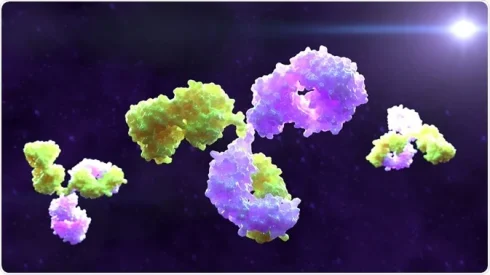

آنتی بادیهای دو میزبانه چیست؟

مقدمهای بر آنتی بادیهای دو میزبانه یا Bispecific Antibodies در حالی که آنتی بادیهای مونوکلونال[بیشتر بخوانید]